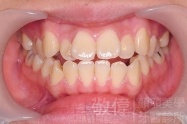

變臉矯正,原來戽斗妹跟大歪臉變成自信正妹

經由本院3D數影X光影像儀分析、與3D齒顎顏矯正技術,再配合口腔顎面正顎專科醫師施以正顎手術治療,雙方共同合作,使患者臉部外觀有很好的改善,大歪變小歪,產生了天南地北的大改變,她的人生也整個變得不一樣。

因為矯正與正顎手術的配合,使「戽斗妹」變成了「陽光正妹」,完全的改變了她的人生,在面對各種場合、與人交際都散發出自信微笑。所以,奉勸家長,如果小朋友有臉顎畸型的問題,應該考慮配合做這種簡單、安全、有效的正顎手術。

「3D齒顎顏矯正」,不止矯正您的牙齒,也會改變您的人生。「治療前」和「治療後」出社會的人生際遇一定會截然不同。